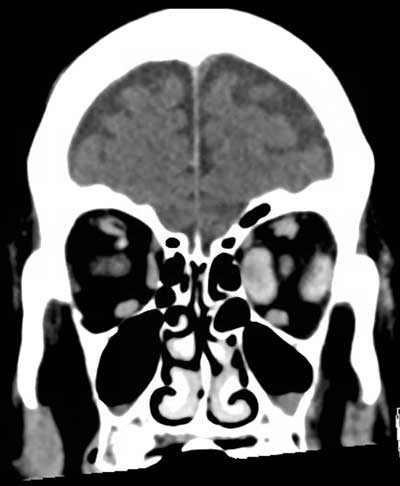

Figure 2

Coronal reconstructions of contrast-enhanced brain CT show fusiform thickening of the left medial and lateral rectus muscles as well as slight thickening of the left superior rectus muscle.